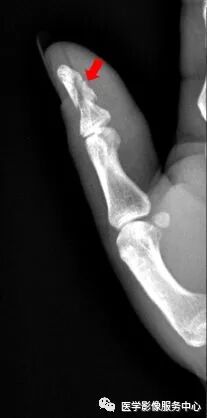

(一)手部

右手拇指远节指骨甲粗隆游离骨碎片影

右手拇指末节指骨见数条骨折线,骨折端对位对线尚可,右手拇指末节指骨粉碎性骨折。